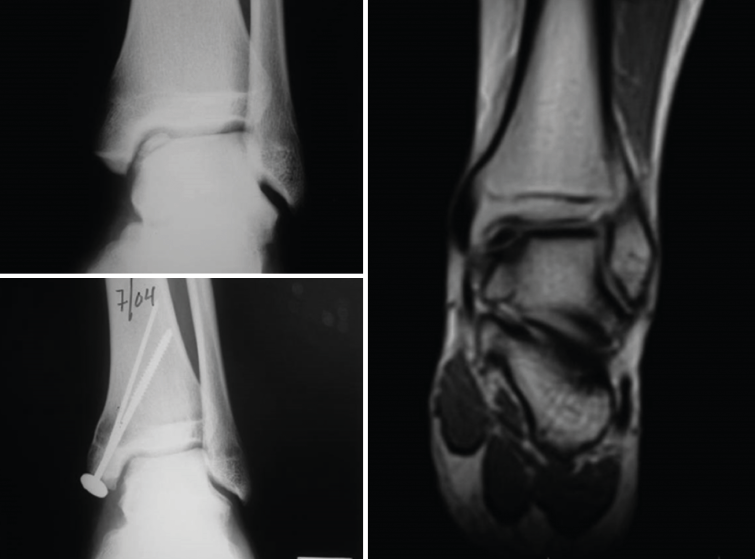

Figure 19. Cartilage regeneration in the ankle joint after Instant CEMTRO Cell (ICC) treatment. The radiological view shows the appearance of the lesion before and after treatment. The magnetic resonance imaging view 6 months after implantation shows the start of joint cartilage regeneration.

The clinical results were correlated to the radiological findings, revealing correct graft integration and regeneration of the cartilage (Figure 19).